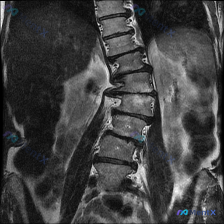

这张胸腰段MRI显示脊柱侧弯和黑盘征,你会直接诊断退变性侧弯吗?

整理到一张脊柱MRI影像,先放核心信息: - 序列:冠状位 T2 加权成像 - 部位:腰椎及胸腰段 - 主要征象: 1. 胸腰段明显向左侧凸,伴椎体旋转、侧倾,顶点在中下胸椎至上腰椎段 2. 几乎所有可见椎间盘 T2 信号显著降低(“黑盘征”) 3. 侧弯凹侧椎间隙窄、凸侧宽,部分节段高度丢失明显...